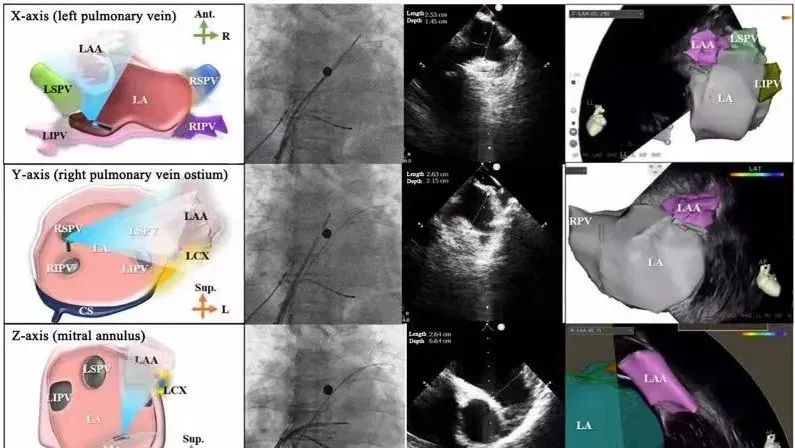

一種與心導(dǎo)管檢查相結(jié)合的超聲心動(dòng)圖診斷新興技術(shù),通過將超聲探頭置于心腔內(nèi)部,發(fā)射并接收超聲信號,來精確獲取心臟解剖結(jié)構(gòu)、心臟血流動(dòng)力學(xué)等信息的實(shí)時(shí)成像。與其他影像技術(shù)相比,ICE技術(shù)具有操作簡單、無輻射、安全性高、手術(shù)效率高、實(shí)用等優(yōu)勢,ICE在很大程度上有望取代經(jīng)食道超聲心動(dòng)圖(TEE),成為電生理和結(jié)構(gòu)性心臟病領(lǐng)域的理想成像方式。

目前ICE技術(shù)已被應(yīng)用于左心耳封堵、房顫射頻消融、二尖瓣成形、房間隔缺損封堵等多種心臟介入手術(shù),應(yīng)用場景主要圍繞心臟電生理、結(jié)構(gòu)性心臟病等領(lǐng)域,目前以電生理應(yīng)用為主。數(shù)據(jù)顯示,我國結(jié)構(gòu)性心臟病介入器械市場規(guī)模已從2017年的4億元增長至2021年的20億元,年復(fù)合增長率達(dá)48.3%;預(yù)計(jì)到2025年,該市場規(guī)模將達(dá)到104億元,可以預(yù)見ICE市場規(guī)模也將同步高速增長,未來市場發(fā)展空間廣闊。

心腔內(nèi)超聲(ICE)技術(shù)壁壘極高,國內(nèi)主要廠商核心部件仍舊為進(jìn)口,集成了超聲和圖像處理最前端技術(shù),包括超聲探頭、線纜、軟件成像算法等,是當(dāng)前內(nèi)窺超聲方向最具挑戰(zhàn)的領(lǐng)域。ICE的應(yīng)用經(jīng)歷了2D平面成像、3D三維立體成像、以及4D的實(shí)時(shí)三維立體成像階段。